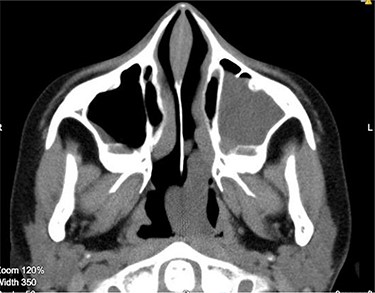

Under general anaesthesia, a large congested mass was seen extending from the left maxillary antrum into the choana (Fig. 3).

The cystic component of the ACP seen within the left nasal cavity on nasal endoscopy.